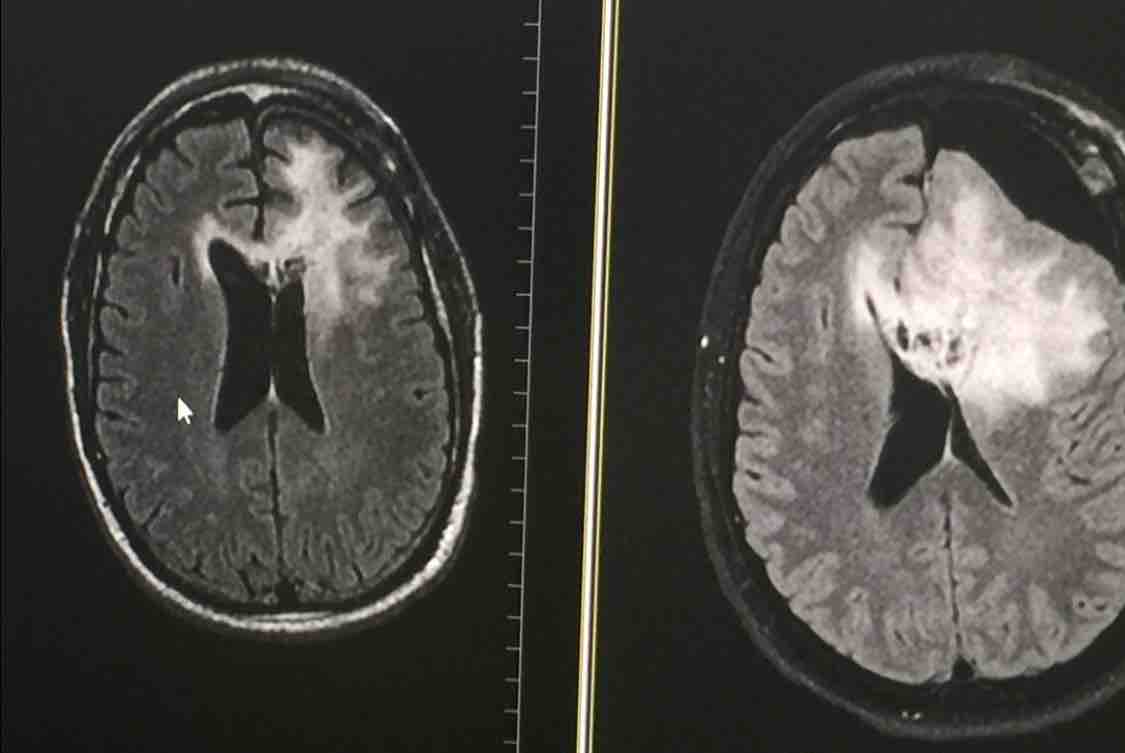

A word of advice......Live today like it is your last day on earth. Hearing the Doctor tell you that you have a Brain Tumor is bad news no matter how you try and spin it. Having the pathology report come back to tell you that the type of Brain Tumor you have is Glioblastoma-GBM is even worse news. Finding out that no one has lived from this tumor ruins the best of days. I am an eternally optimistic person. Always the life of the party. Always happy. But knowing I probably will not make it to the end of the year can definitely make for a sad and bad day. I have a lot to be thankful for. All my friends that have reached out and outpouring of “well wishes” and prayers that I have received have been emotionally overwhelming. I can never attempt to put into words how much my heart is bathed in the love and appreciation of feeling the awesome joy I feel from you. I truly appreciate the love.

I have been asked by a lot of you. “Is there anything I can do to help?”. The only thing I want for the rest of my life is to make sure my 13 year old daughter is taken care of. I am so grateful that the world’s top Neurosurgeon at UCLA was able to do my surgery. I have to admit it was kind of trippy them waking me up during Brain Surgery to talk to me and ask me questions. It was explained to me later that this was so they did not cut the wrong part of my brain out. I was so impressed by my treatment at UCLA, that my daughter now wants to go there. This is kind of a big deal because I went to USC. If I had a wish it would be to live to see her attend UCLA. I will remain positive and pray.

Since my surgery I have accepted into a clinical trial called www.MoonShot2020.org Even though my type of brain tumor KILLS EVERYONE! I have hope that I will be the 1 person who lives.